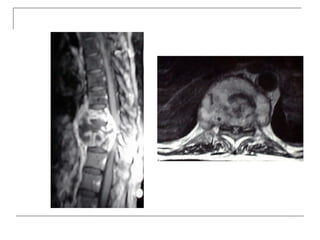

MRI

 -better soft tissue visualization

 -disc

 -ligaments (ALL,PLL)

 -nerves (spinal cord, roots)

 -bone marrow

 -pus collection